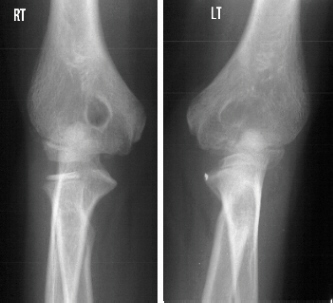

The patient is an 11 year old, otherwise completely healthy

boy, who presented for evaluation of his left arm. He states he

has always had limited range of motion of his left arm, however,

his mother states that it was not until recently she became concerned.

The patient is right hand dominant. This does not cause him any

functional problems and he has no pain. The mother and boy are

concerned because the right and left arms are different. The left

arm demonstrates a shoulder with full range of motion (ROM) and

strength 5/5. The elbow has a flexion from 0 to 135 degrees, but

the forearm is fixed in 45 degrees of pronation without active

or passive supination. The wrist has full ROM with some hyper-mobility,

especially in radial and ulnar deviation. The strength is 5/5

in elbow flexion/extension, wrist flexion/extension and grip.

He is neurovascularly, intact. The right arm also demonstrates

normal motion at the elbow with flexion from 0-135 degrees but

limited supination from 0-50 degrees and pronation from 0-20 degrees.

The remainder of his exam was normal.